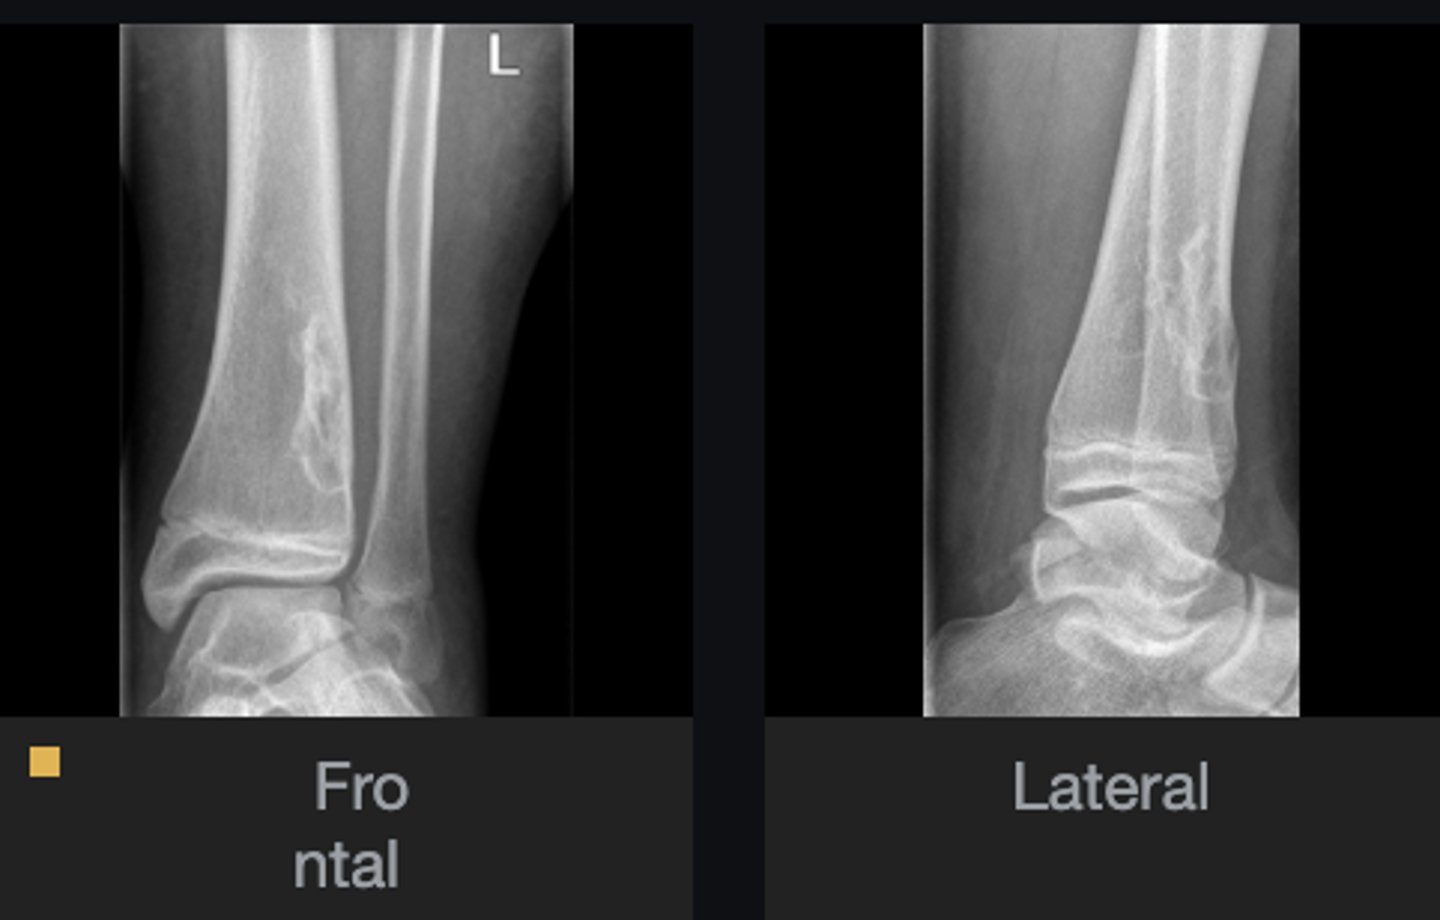

- Anterolateral distal tibia

- Metaphysis

- Septation

- Cortical thinning

- Geographic

- Sclerotic border

- Fibrous matrix

Describe the lesion

<p>Describe the lesion</p>

Non-Ossifying Fibroma

Diagnosis?

<p>Diagnosis?</p>

- Look for fracture

- Refer to orthopedist

Next step?

<p>Next step?</p>